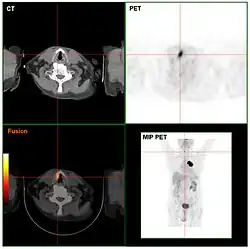

Computed tomography (CT) and positron emission tomography (PET) scans are similar to MRI, but rely on different imaging techniques (X-rays and ionizing radiation, respectively). A variation of CT known as contrast CT also requires the subject to take in a contrast medium called a radiocontrast (typically by oral consumption, enema, or injection). Positive radiocontrast agents such as barium sulfate increase the body's X-ray attenuation, causing the tissue containing them to appear whiter in the X-ray image. Meanwhile, negative agents such as carbon dioxide gas allow X-rays to pass through them easily, causing the tissues containing them to appear darker.[49]

Like magnetic resonance imaging, CT scans use numerous methods to display and measure data, including sequential CT (where the CT table steps from location to location), spiral CT (where the entire X-ray tube is spun around the subject), and electron beam tomography (where only the electron paths are spun using deflection coils). PET scanners don’t have quite as much hardware variation and instead use different radiotracers depending on what the imaging target is. Note that radiotracers are distinct from radiocontrasts; the former relies on radioactive decay to trace its path while the latter is absorbed into specific tissue and affects that tissue's X-ray attenuation. Because these methods are not mutually exclusive, PET and CT can be performed simultaneously using PET-CT scanners, which are used for the majority of modern PET scans.[50]

Either or both of these methods can be used in conjunction with maximum intensity projection (MIP) to convert the scan data into a 3D image. This can be difficult to accomplish due to artifacts created by respiration and bloodflow, which can appear as abnormalities to an untrained eye; however, it's possible to distinguish these artifacts from real disease so long as careful attention is paid to them.[51] When done well, CT and PET scans taken with MIP are excellent for identifying small abnormal tissue growths, especially in the lungs. Scans taken with MIP for this purpose tend to have higher significance than averaged images created with traditional CT.[52]

MIP imaging is also used with magnetic resonance angiography, and research has indicated that it could feasibly be used with MRI.[53] At least one study has shown that MIP MRI actually significantly outperforms single-slice MRI when used by neural networks to classify lesions based on malignancy.[54]